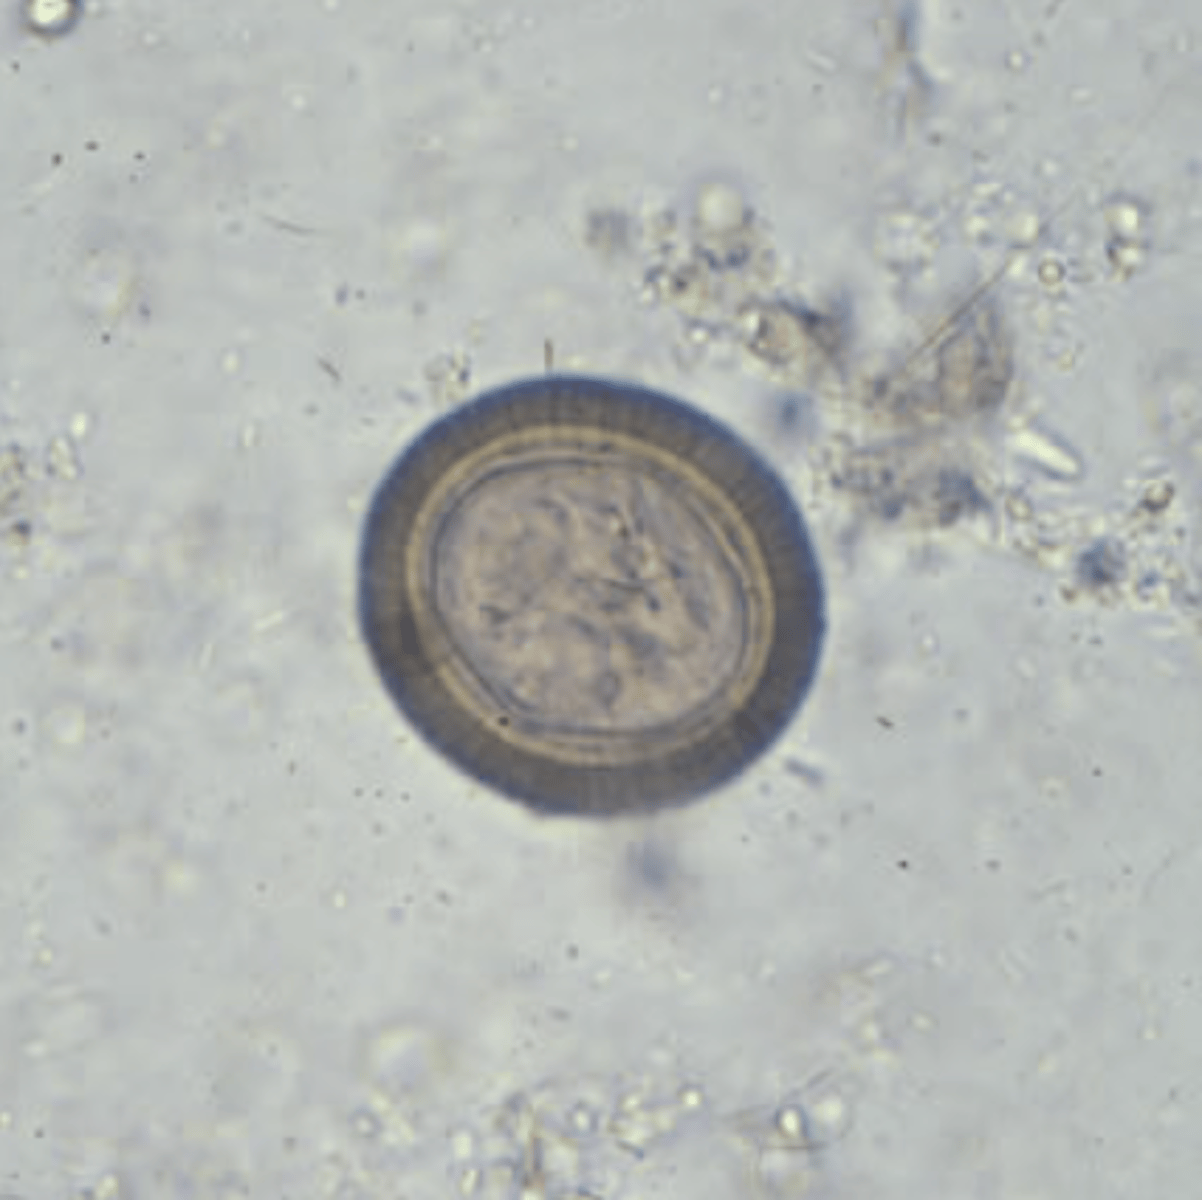

Taenia spp. egg